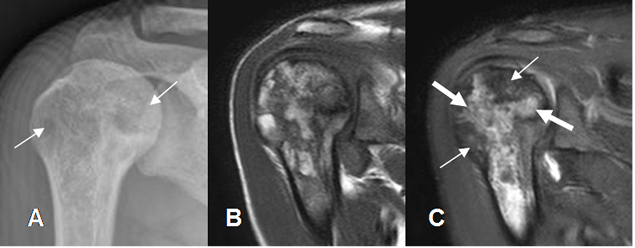

Fig 45. Anemia drepanocítica.

A: Rx AP. Zonas de disminución en la densidad de la cabeza humeral.

B: RM coronal en T1 y C: RM coronal en STIR. Lesiones geográficas y parcheadas.

Algunas son hiperintensas en STIR por edema óseo (Flechas gruesas) y otras hipointensas por infarto (Flechas delgadas).